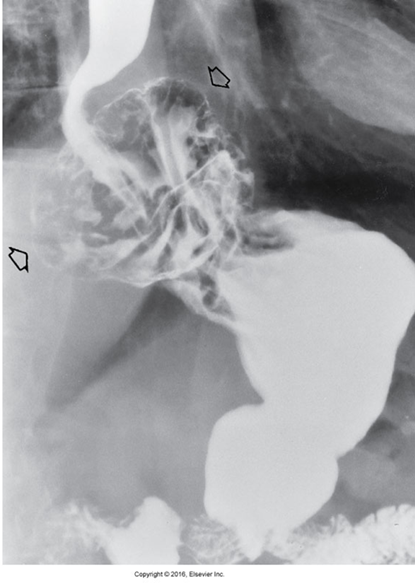

Hiatal Hernia

Protrusion of a portion of the stomach into the thoracic cavity through the esophageal hiatus in the diaphragm.

Radiological Appearance:

Appear as soft tissue mass in posterior mediastinum with air fluid level.